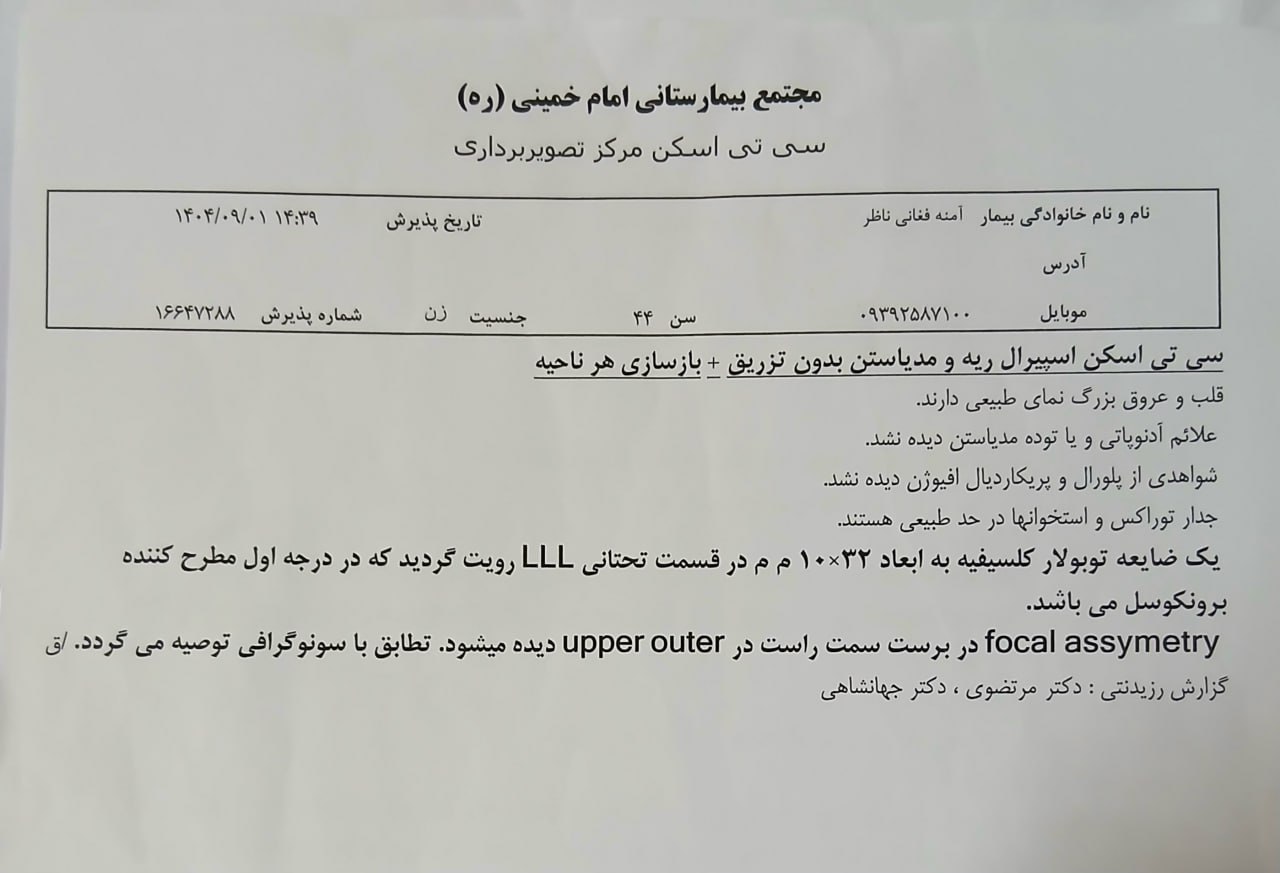

(تصویر مربوط به این مراجعه نیست) Other:

(تصویر مربوط به این مراجعه نیست) Other:

(تصویر مربوط به این مراجعه نیست) Other:

(تصویر مربوط به این مراجعه نیست) Other:

(تصویر مربوط به این مراجعه نیست) Other:

(تصویر مربوط به این مراجعه نیست) Other:

(تصویر مربوط به این مراجعه نیست) Other:

(تصویر مربوط به این مراجعه نیست) Other:

(تصویر مربوط به این مراجعه نیست) Other:

(تصویر مربوط به این مراجعه نیست) Other:

(تصویر مربوط به این مراجعه نیست) Other:

(تصویر مربوط به این مراجعه نیست) Other:

(تصویر مربوط به این مراجعه نیست) Other:

(تصویر مربوط به این مراجعه نیست) Other:

(تصویر مربوط به این مراجعه نیست) Other:

(تصویر مربوط به این مراجعه نیست) Other:

(تصویر مربوط به این مراجعه نیست) Other:

(تصویر مربوط به این مراجعه نیست) Other:

(تصویر مربوط به این مراجعه نیست) Other:

(تصویر مربوط به این مراجعه نیست) Other:

(تصویر مربوط به این مراجعه نیست) Other:

(تصویر مربوط به این مراجعه نیست) Other:

(تصویر مربوط به این مراجعه نیست) Other:

(تصویر مربوط به این مراجعه نیست) Other:

(تصویر مربوط به این مراجعه نیست) Other:

(تصویر مربوط به این مراجعه نیست) Other:

(تصویر مربوط به این مراجعه نیست) Other:

(تصویر مربوط به این مراجعه نیست) Other:

(تصویر مربوط به این مراجعه نیست) Other:

(تصویر مربوط به این مراجعه نیست) Other:

(تصویر مربوط به این مراجعه نیست) Other:

(تصویر مربوط به این مراجعه نیست) Other:

(تصویر مربوط به این مراجعه نیست) Other:

(تصویر مربوط به این مراجعه نیست) Other:

(تصویر مربوط به این مراجعه نیست) Other:

(تصویر مربوط به این مراجعه نیست) Other:

(تصویر مربوط به این مراجعه نیست) Other:

(تصویر مربوط به این مراجعه نیست) Other:

(تصویر مربوط به این مراجعه نیست) Other:

(تصویر مربوط به این مراجعه نیست) Other:

(تصویر مربوط به این مراجعه نیست) Other:

(تصویر مربوط به این مراجعه نیست) Other:

(تصویر مربوط به این مراجعه نیست) Other:

(تصویر مربوط به این مراجعه نیست) Other:

(تصویر مربوط به این مراجعه نیست) Other:

(تصویر مربوط به این مراجعه نیست) Other:

(تصویر مربوط به این مراجعه نیست) Other: